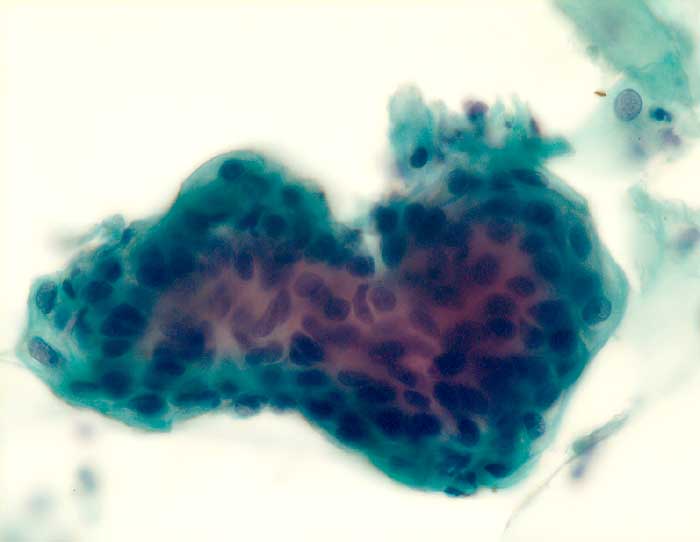

g/ Seröses Adenokarzinom des Endometrium

Seröses Adenokarzinom des Endometrium

Die Zellkerne der serösen Adenokarzinome sind in den meisten Fällen hochgradig atypisch. Das Zellbild gleicht entsprechend demjenigen eines wenig differenzierten endometrioiden Adenokarzinoms. Da das seröse Karzinom anders als das endometrioide Karzinom nicht Folge eines Hyperöstrogenismus ist, zeigen die meist postmenopausalen Patientinnen keinen hohen Aufbau des Vaginalepithels im PC-Abstrich.